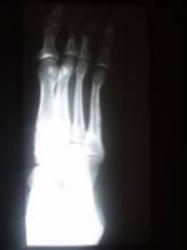

Протокол исследования. Левая стопа в пределах нормы. Справа определяется аномалия развития стопы в виде истинной четырехпалости (отсутствие 5 плюсневой кости и фаланг 5 пальца) – 1. Определяется гипоплазия фаланг пальцев, плюсневых костей и других костей стопы по сравнению с левой стороной. На рентгенограмме стопы, произведенной в косой проекции (2) чётко дифференцируются медиальная, промежуточная и латеральная клиновидные кости. Кубовидная и ладьевидная кости не дифференцируются. Определяется некоторая деформация и гипоплазия передних отделов таранной и пяточной костей. На боковой рентгенограмме стопы (3), произведенной в положении стоя (под нагрузкой) щель подтаранного сустава не дифференцируется, что свидетельствует о частичном синостозе между указанными костями. Головка таранной кости несколько укорочена, деформирована, уплощена с выраженным субхондральным склерозом. Она сочленяется с задней поверхностью медиальной, промежуточной и частично латеральной клиновидными костями

Заключение: Аномалия развития правой стопы в виде истинной четырехпалости, с отсутствием кубовидной и ладьевидной костей, частичным синостозом между пяточной и таранной костями. Гипоплазия костей правой стопы. Продольное плоскостопие второй ст.